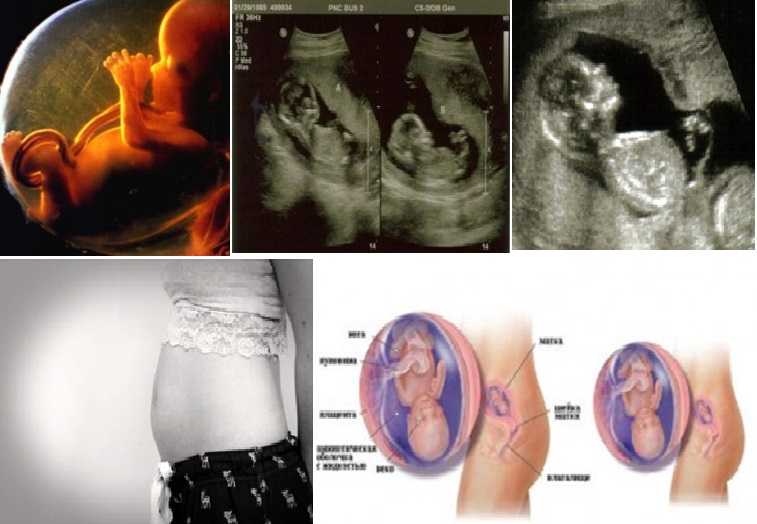

Расположение плода на 15-й неделе беременности: фотографии и иллюстрации